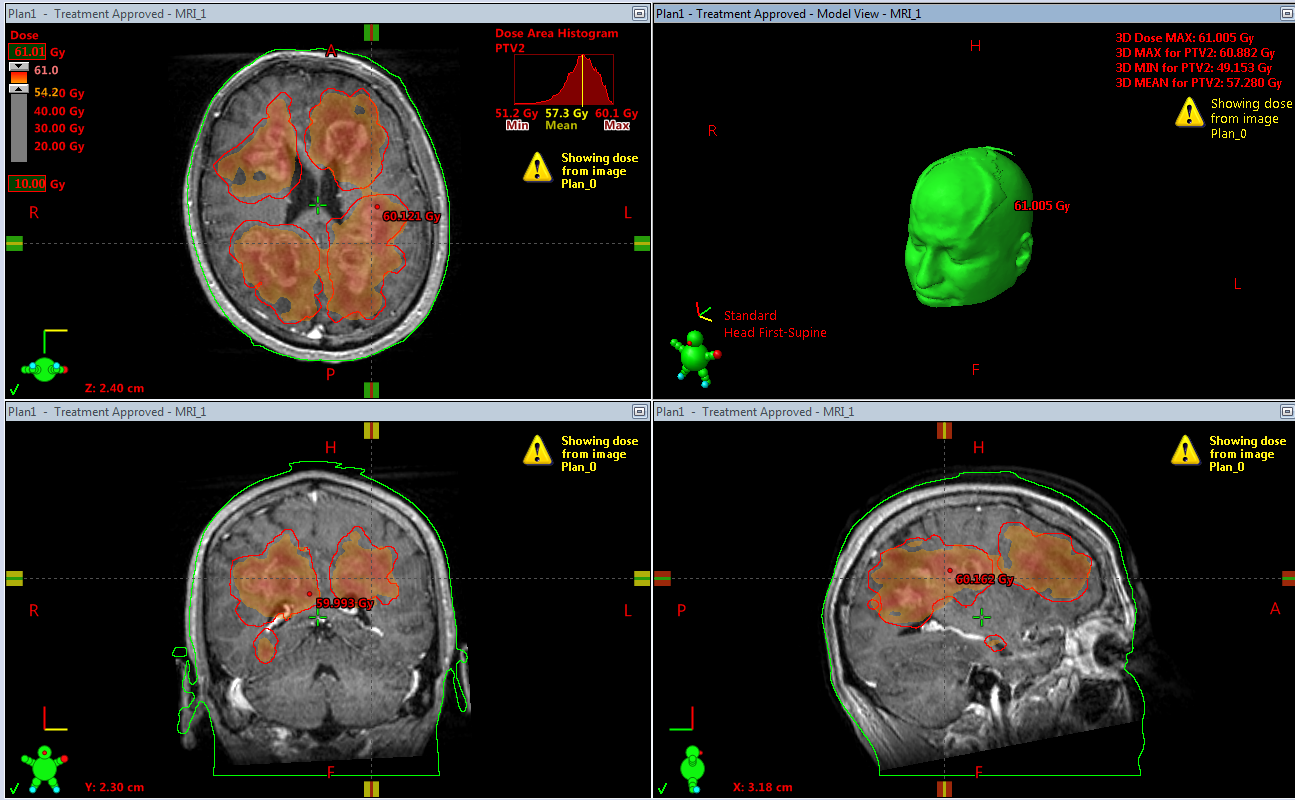

A 38-year old male was admitted to our hospital complaining of progressive memory loss during the last two months. His medical record included heavy smoking (40 pack-years) but was otherwise unremarkable. The results of the neurological examination and laboratory tests were all within normal ranges. An MRI scan of the brain was performed, showing multiple contrast-enhancing space-occupying lesions (Figure 1). The differential diagnosis included brain metastases from some primary tumor such as lung and diffuse multifocal glioma. A thoraco-abdominal CT scan was performed to eliminate the former possibility. Subsequently, a stereotactic biopsy of a single lesion was performed, and the microscopic examination revealed a diffuse astrocytoma, grade II per WHO classification 2007 (Figure 2). At the time of diagnosis, three years ago, we did not perform molecular profiling (IDH mutations, 1p/19q codeletion, ATRX loss, and MGMT methylation status) in central nervous system tumors. Despite the particularly low proliferative index (Ki67: 1-2%), it was decided to be treated aggressively due to high volume disease. He underwent volumetric modulated arc therapy (VMAT) with a simultaneous integrated boost, receiving 54 Gy in 30 sessions with 1.8 Gy per session to the enhancing lesions of the brain and 50 Gy in the peritumoral edema (Figure 3). Concurrent with radiotherapy, he received temozolomide 75 mg/m2. After completing chemoradiotherapy, he continued with adjuvant temozolomide 150 mg/m2 (escalated to 200mg/m2 from cycle two onwards) for 12 months. Since then, he is disease-free with regular MRI/MR spectroscopy imaging (Figure 4). The deterioration of his memory loss halted, and the patient reports no other neurological symptoms.

Figure 3 Dose distribution superimposed with brain MRI. The patient was treated with VMAT with a simultaneous integrated boost, receiving 54 Gy in 30 sessions with 1.8 Gy per session to the enhancing lesions of the brain and 50 Gy to the peritumoral edema.

The role of radiation therapy is also under transformation in the modern era. Historically, whole-brain radiotherapy (WBRT) has been used to treat multifocal/multicentric gliomas. However, WBRT is being questioned, as most failures are traced within the original tumor extent, and high doses cannot be delivered to the entire brain.6,27 Despite the numerous foci in our patient, we opted for targeted radiotherapy considering his young age, favorable histology, and the inability to escalate dose with whole-brain radiotherapy. Therefore, he was treated with a VMAT technique and a simultaneous integrated boost to the contrast-enhancing areas. Concurrent with the irradiation, he received temozolomide 75 mg/m2. After the completion of chemoradiation, he continued with adjuvant temozolomide for 12 months.